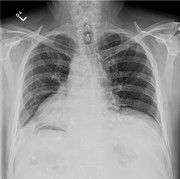

Gastric wall ischemia following massive gastric distension due to peptic pyloric stenosis: a case report

Tatiana Santos and others

Journal of Surgical Case Reports, Volume 2016, Issue 2, February 2016, rjw008, https://doi.org/10.1093/jscr/rjw008